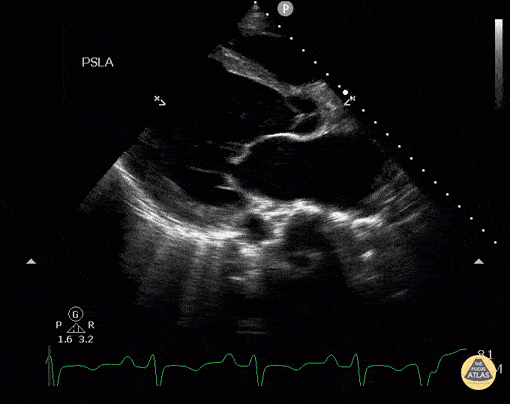

This healthy patient presented 3 months postpartum with progressive dyspnea over the past few weeks found to have new postpartum cardiomyopathy with EF about 10-15% as demonstrated in the parasternal long axis view. Image courtesy of Robert Jones DO, FACEP @RJonesSonoEM Director, Emergency Ultrasound; MetroHealth Medical Center; Professor, Case Western Reserve Medical School, Cleveland, OH View his original post here.